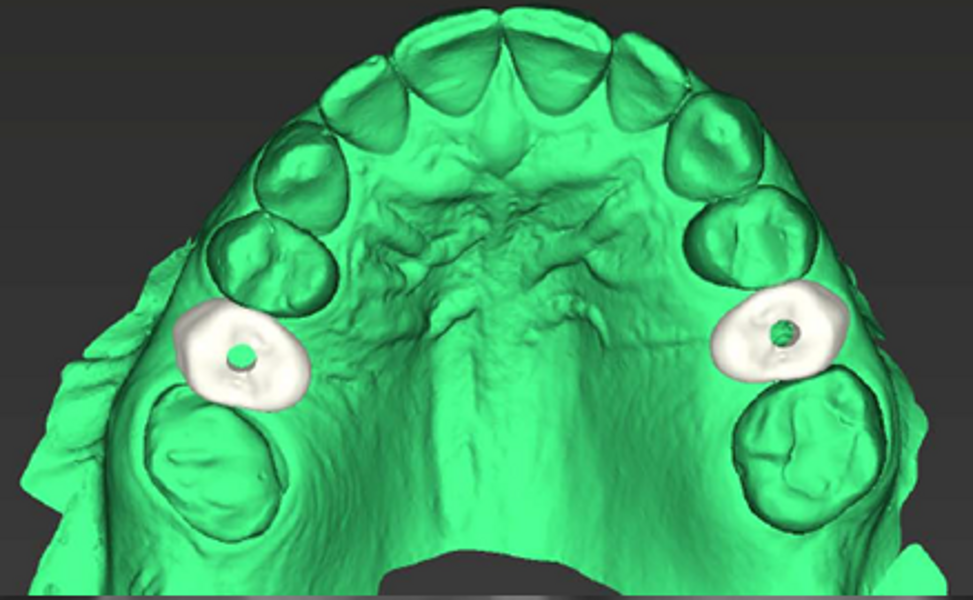

The patient’s maxillary and mandibular arches were scanned using the Straumann SIRIOS system. The scans, along with the DICOM files from the CBCT scan, were sent via Straumann AXS to Smile in a Box (Straumann) for treatment planning, surgical guide design and 3D printing of the model and surgical guides (Figs. 4, 5a–f & Figs. 6a–d).

After evaluation and validation of the plan, it was decided for site #15—where a residual root was present and the bone density was generally soft—that a Straumann BLX (Roxolid, SLActive, regular base) 4.5 × 8.0 mm implant would be placed, along with an M shape Straumann Anatomic Healing Abutment XC (regular base/wide base; gingival height: 1.5 mm). For site #25, extraction of the remaining root was planned and would be followed by the placement of a Straumann BLC (Roxolid, SLActive, regular base) 3.75 × 8.00 mm implant. This narrower site had a visible lamina dura, favourable for achieving primary stability. An M shape Straumann Anatomic Healing Abutment XC (regular base/wide base; gingival height: 1.5 mm) was also selected for this site to support proper soft-tissue emergence during the 60- to 90-day healing period. Owing to the expected post-extraction gaps between the implants and buccal bone walls, cerabone plus (botiss biomaterials) was planned to be used for grafting.